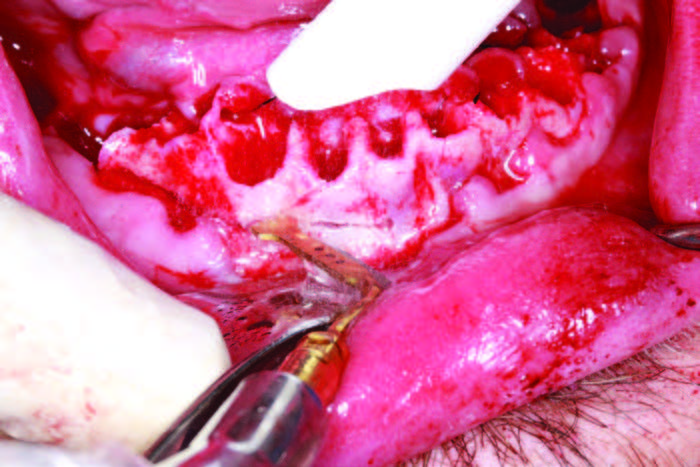

If the tooth is ankylosed or multi-rooted, then a Piezo surgical device is used to sever the periodontal ligaments (Figure 4c). It uses micro vibrations to allow the various inserts to remove bone, cut ligaments, and level osteotomies with a minimum of bleeding. It practically stops bleeding due to the movement of bone, the sealing of capillaries, and saline irrigation during the procedure. Extractions of all the mandibular teeth were done, and a caliper was used as measured in the reformatted CBCT scan (3DDX) to mark the alveolus and begin osteoplasty at each socket for the planned implant platform placement (Figure 5a). The osteoplasty was performed atraumatically using the Piezosurgery unit, and, after a cut was made buccal to lingual, a diamond insert was used to smooth all sharp edges and to level the implant sites using the Piezo surgical device (Figures 5b and 5c). A 10,600-nm CO2 laser (LightScalpel) was used to disinfect the sockets (Figure 6a). The laser uses water as its main chromophore and removes tissue by vaporization while limiting any zone of necrosis. Bacterial kill within the extraction socket, granuloma removal, and hemostasis are all accomplished with the use of this true spatially accurate laser device. In fact, use of the laser to trim tissue around abutments and permucosal healing abutments, treat peri-implantitis, and remove frena to decrease tissue pull on implants are all indicated procedures for this wavelength of CO2 laser.[3] Trimming of hypertrophic tissue during maxillary provisional placement allows for tissue modification without bleeding (Figure 6b).